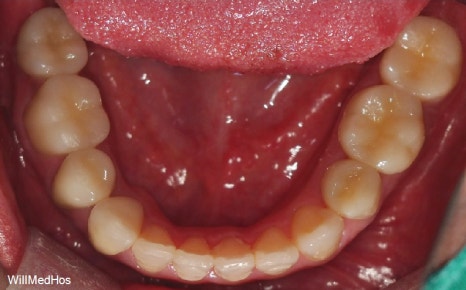

위의 사진이 최종 치료 사진 입니다. 뼈이식, 신경치료 후 크라운, 임플란트 치료를 진행 하였고

최종 기간은 10개월 정도 소요 되었습니다.

▲ 최종 완료 구강 사진